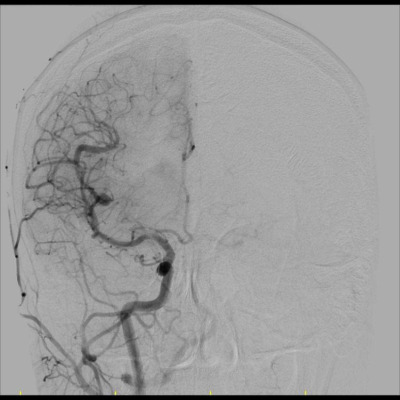

29 yaş, K

Baş ağrısı

Arteriyovenöz Malformasyon

AVM